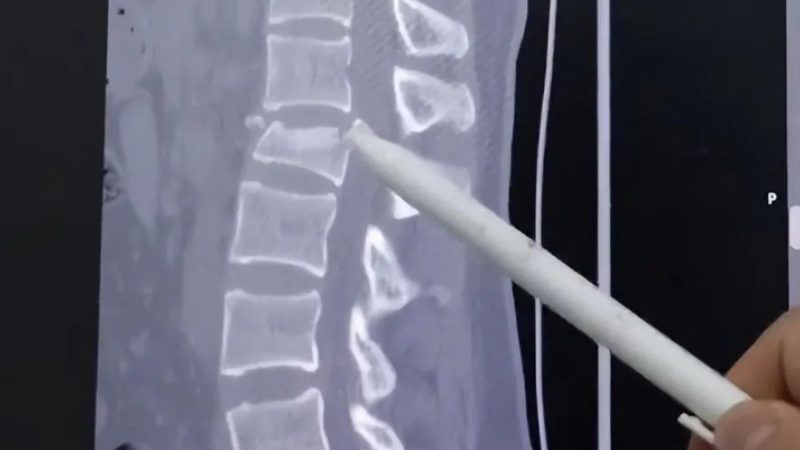

Medical experts from Beijing’s Xuanwu Hospital, including orthopaedic specialist Dr Wang Juyong, described the case as a serious emergency. He explained that the impact had severely crushed the patient’s spinal vertebrae, with bone fragments shifting backwards and compressing the spinal canal, leaving only about one-third of its normal space.

Doctors also noted that the patient had already begun showing signs of neurological impairment, including loss of control over bowel and bladder functions, making the situation critical and time-sensitive.